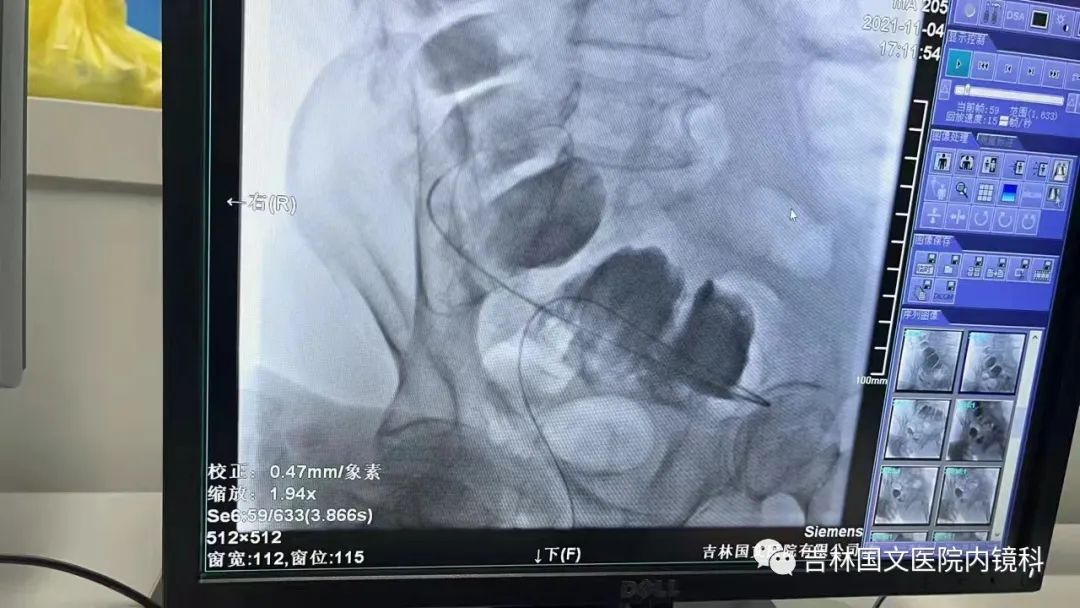

腸道支架置入

這是一位腸癌的患者,腫物生長(zhǎng)在乙狀結(jié)腸,將腸腔堵得只剩一個(gè)小孔,糞便自然很難通過,腸梗阻的癥狀使患者十分難受,已多天未排氣排便,患者十分瘦削,開始侯主任未借助任何工具探查一番,結(jié)果就是腸道太迂曲了,實(shí)在無法順利將導(dǎo)絲置入,通過邢主任使用腸鏡在前面引路一直到達(dá)病變部位,這時(shí)候侯主任將帶有外套管的導(dǎo)絲從活檢口插入,外套管抵在小孔處,導(dǎo)絲順利進(jìn)入,第一步成功。第二步就是將支架順著導(dǎo)絲送入指定位置,又是一大難關(guān),導(dǎo)絲十分軟,缺乏支撐力,腸道的彎曲十分陡峭,一用力支架抵在腸道低處,患者痛感極強(qiáng),只能另想辦法,嘗試多次后,在兩位主任的豐富經(jīng)驗(yàn)和堅(jiān)持不懈的努力下,支架順利置入,為患者解除了痛苦。